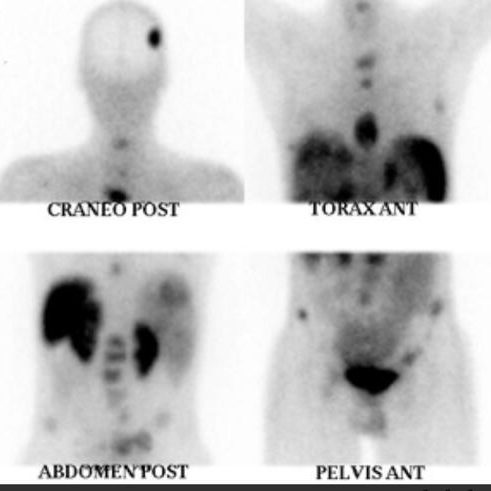

¿Cómo se realiza una gammagrafía ósea?

Una gammagrafía ósea implica inyectar una cantidad muy pequeña de material radiactivo (marcador) dentro de una vena. La sustancia viaja a través de la sangre hasta los huesos y órganos. A medida que esta va desapareciendo, emite un poco de radiación. Esta es detectada por una cámara que lentamente escanea el cuerpo.

¿Cuánto tiempo se tarda en hacer una gammagrafía ósea?

Toma imágenes del marcador que hay en sus huesos. El técnico puede solicitarle que cambie de posición durante el procedimiento. Esto ayuda a obtener imágenes desde diferentes ángulos. Una gammagrafía ósea de todo el cuerpo tarda aproximadamente 1 hora en completarse.

¿Que detecta la cámara gamma?

La cámara gamma detecta las emisiones de energía de la radiosonda en su cuerpo y las convierte en una imágen. La cámara gamma de por sí no emite ninguna radiación. Tiene detectores de radiación denominados cabezas de cámara gamma.